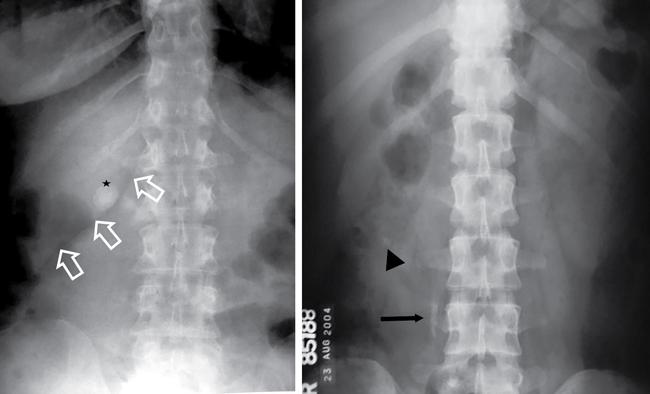

UNDERSTANDING THE ADULT ABDOMINAL RADIOGRAPH: TECHNIQUES AND INTERPRETATION Tanvi Modi Radiography of the abdomen is a common practice for the evaluation of abdominal organs. The anatomy and pathology of digestive, hepatobiliary and genitourinary systems can be assessed using radiographs, either as a stand-alone practice or as a primary imaging modality followed by contrast studies, ultrasound or cross-sectional imaging. In addition, abnormalities of the musculoskeletal or integumentary system can also be deduced on the basis of abdominal radiographs. This chapter intends to give an overview on the techniques and positioning in abdominal radiography as well as interpretation of normal and abnormal features. While superior imaging modalities such as ultrasound, computed tomography (CT), magnetic resonance imaging, capsule endoscopy and the likes have taken over abdominal imaging by and large, radiography still holds a pivotal role in certain situations and conditions, such as: The standard abdominal radiograph is taken in supine position and anteroposterior projection. This is also popularly known as the KUB (kidneys-ureters-bladder) radiograph. Previously, supine as well as erect radiographs were performed in all patients; however, this is not commonly done due to high-radiation dose. For all indications of abdominal radiography, including acute abdomen, supine radiographs are sufficient in terms of radiographic diagnosis, with the exception of perforation for which an erect chest or lateral decubitus radiograph can be performed if there is clinical suspicion. Patient should lie supine on the imaging table with median sagittal plane at right angles to the table and coincident with the midline of the table (Fig. 7.1.1.1). The body is divided into equal right and left halves by the median sagittal which passes through the sagittal suture of the skull. Pelvis should be adjusted so that the anterior superior iliac spines are equidistant from the table top. Gonadal shields, in the case of male patients, should be placed with the upper edge of the shield at the level of pubic symphysis. Although rarely used for female patients, these should be positioned between the anterior superior iliac spines and the pubic symphysis. The centre point of the image receptor should be approximately located at a point 1 cm below the line joining the iliac crests. The X-ray beam should be in a vertical direction, perpendicular to the table top and image receptor at the centre point. Collimation should be such that the soft tissue and subcutaneous region along lateral aspects of the abdominal cavity should be covered within the image. Also, the superior extent involving diaphragm and inferior extent involving the inferior pubic rami is important to look for any lower chest pathologies or any inguinal hernia. 35 × 43 cm (14 × 17 inches) in portrait orientation. On an average, abdominal radiograph exposes a patient to a dose of approximately 1.5 mSv, which is equivalent to 75 chest radiographs or 1/6th dose of a standard CT of the abdomen. The entrance skin dose is approximated to be 4 mGy. At such an effective dose, the additional lifetime risk of fatal cancer is 1 in 30,000. The exposure time is kept short. Patient is asked to exhale completely and hold their breath, with exposure taken at this point of full expiration to ensure imaging of abdominal organs in their natural positions. Modifications of this technique can be made depending on patient habitus and clinical condition. Kilovoltage peak (kVp) should be set to allow adequate visualization of abdominal soft tissue structures as well as semiopaque renal and biliary calculi. Average kVp is set at 70–85 kV. 102 cm (40 inches) Grids are commonly used to reduce scatter radiation. Placement of side marker on the image receptor at the time of radiographic exposure is essential. Bowel pattern depiction should be such that there is minimal lack of sharpness. Standard guidelines for abdominal radiography dictate that the radiograph should extend from the diaphragm up to the level of inferior pubic rami and must include the lateral abdominal wall musculature. The abdomen is divided into four quadrants on the basis of two perpendicular lines (Fig. 7.1.1.7). The vertical line passes through the mid sagittal plane and crosses the umbilicus and symphysis pubis. The horizontal line is a transverse line across the umbilicus at 90 degrees to the vertical line and is situated at the level of L4–L5 intervertebral disc. The quadrants are as follows: Another division system is dividing the abdominopelvic cavity into nine regions using two vertical and two horizontal planes (Fig. 7.1.1.8). The vertical planes, also known as the right and left lateral planes, are parallel to the midsagittal plane between midline and anterosuperior iliac spines on either side. Of the two horizontal planes, the upper transpyloric plane is at the level of lower border of L1 and the lower transtubercular plane is at the level of L5. The nine regions are: On a standard radiograph, the exposure should be such that the stomach, bowel loops, outlines of liver, spleen, kidneys, psoas muscles should be well identified. Also, lumbar transverse processes should be seen. Arch of the pubic symphysis should be visible to evaluate bladder region. A well-centred film without rotation will demonstrate bilaterally symmetrical lower ribs, iliac wings, ischial spines and obturator foramina. Different structures seen on an abdominal radiograph can be classified into five basic densities: Identification of different structures depends on the relative degree of contrast between their densities. The demarcation is clearer in chest and is diminished in abdomen due to relative similar soft tissue density of various structures. On a normal radiograph, relatively large amounts of gas in stomach and colon with minimal small bowel gas can be seen. Further, colonic gas can vary from negligible to extensive, mimicking obstruction pattern; however, usually the gas is enough to delineate colonic haustral pattern. Faecal matter gives a mottled appearance to colonic gas. Short-air fluid levels on an erect radiograph may be seen even in normal cases. The normal appearance of small bowel loops on an abdominal radiograph follows the rule of threes: Stomach is seen in the left upper quadrant and is visualized when distended with air. It is commonly seen extending from T11 to L2 level. Common feature identifying the stomach is the fundal gas which is usually seen as an air fluid level within the gastric lumen. Small bowel loops are distributed to the centre of the abdominal cavity and large bowel loops are peripheral. Duodenum is predominantly situated in right upper quadrant. It extends to left upper quadrant in the region of duodenojejunal flexure. Jejunum occupies the left upper and lower quadrants and is easily identified due to the presence of thick, numerous, closely spaced valvulae conniventes (Fig. 7.1.1.9A). The ileum occupies both lower quadrants and extends into right upper quadrant. Ileum has few and less prominent valvulae as compared to jejunum (Fig. 7.1.1.9B). Ascending and descending colon are retroperitoneal and have relatively fixed positions along lateral aspect of the abdominal cavity on either side. Transverse and sigmoid colon, on the other hand, may have a variable position due to their mobility along mesocolon and redundant pattern. These can be identified with confidence on account of haustrations and faecal matter (Fig. 7.1.1.10). Haustrations are usually well seen in ascending and transverse colon and poorly delineated beyond splenic flexure. Caecum is in the right lower quadrant, though it may be mobile or pulled up. Rectal gas is usually seen in the midline at the level of pelvis and its presence rules out large bowel obstruction. All these positions may vary due to anatomical conditions such as malrotation or pathological conditions, for example volvulus. Liver, spleen and renal outlines cannot be completely traced with precision due to the overlap by bowel loops. On a frontal projection, the liver appears as a triangular structure occupying right and left hypochondrium and epigastric region. Occasionally, the right lobe may be seen extending lower than the right renal shadow. This is a normal variant known as Reidel’s lobe. Gall bladder is situated in the posterior and inferior region of the liver and any pathology of the gall bladder should be looked for in this region. On a lateral radiograph, the gall bladder is anterior to the midcoronal plane. This helps in distinguishing gall bladder calculi from renal calculi, which will be more posteriorly situated. Spleen is seen in left upper quadrant/left hypochondrium, flushed to left lower ribs and left hemidiaphragm. Pancreas is present in the epigastric region (right and left upper quadrants) and is usually not identified in the absence of a pathology. The kidneys are bean-shaped retroperitoneal organs which are seen on either side of the vertebral column and lateral to psoas muscles. Due to the presence of liver on the right side, this kidney is slightly lower in position as compared to its contralateral counterpart. The visualization of kidneys on radiographs is facilitated by the surrounding fatty capsule. Kidneys lie between T11–12 and L2 level, with left kidney 1 cm higher than the right. Psoas muscle shadow can be normally seen along lateral aspect of lumbar spine bilaterally and is mildly concave (Fig. 7.1.1.11). Abdominal wall muscles are not routinely assessed on radiography; however, inclusion of lateral abdominal wall (muscles as well as subcutaneous plane) is a must while performing radiography. The flank stripe or the properitoneal fat stripe is a fat density linear concavity seen along lateral abdominal wall (Fig. 7.1.1.11). It is bound by the paracolic gutters and air-filled ascending and descending colon. All the solid organs in the abdomen are identified due to the fat density outlining them. Distortion of these fat lines helps in identifying organomegaly or focal mass lesions. The dome of urinary bladder is outlined by fat, which aids in differentiating its density from other soft tissue structures of the pelvis. Not all calcifications seen on abdominal radiograph are abnormal. Some may depict age-related changes such as vascular calcifications involving abdominal aorta, pelvic vessels, splenic artery in the region of left upper quadrant. Within the pelvis, phleboliths may be seen and mistaken for urinary calculi. Assessment of lumbosacral spine, iliac bones and femoral heads can be made on the basis of plain radiography. Degenerative changes may be commonly seen. Lower ribs can also be evaluated for pathologies. Dilated small bowel loops with rounded soft tissue density in midline over umbilical region suggests obstruction secondary to umbilical hernia. Pneumoperitoneum must be looked for in all cases of acute abdomen. While erect chest and left lateral decubitus radiographs can detect even 1 mL of free air, there are multiple signs on supine radiograph to suggest this diagnosis, for example Rigler’s sign, falciform ligament sign, football sign (Figs. 7.1.1.24 and 7.1.1.25). Retroperitoneal perforation may demonstrate air outlining psoas muscles and retroperitoneal organs. Small amount of free air may persist in the abdominal cavity up to 3 weeks after surgery, although it usually resolves within a week. Clinical history is important in such cases. Air foci within the bowel wall may represent bowel ischaemia/strangulation. Linear gas patterns in right hypochondrium may be due to two causes, that is pneumobilia and pneumoporta. The former can be seen normally postbiliary surgery, sphincterotomy, ERCP or in the case of abnormal fistulous communication between bowel and biliary tree (Fig. 7.1.1.26A). Pneumoporta (Fig. 7.1.1.26B) is a red flag and warrants further investigation to look for conditions such as mesenteric ischaemia and toxic megacolon. Pneumobilia is more centrally located whereas air shadows in pneumoporta are seen reaching up to periphery of liver. Air foci over renal shadows (Fig. 7.1.1.27), gall bladder or pancreas, in the absence of recent procedural history, suggest fulminant infection and mandate urgent intervention. Central midline calcific foci between T9 and T12 vertebrae can be attributed to calcific pancreatitis (Fig. 7.1.1.28). In the left upper quadrant, areas of calcification seen involving a shrunken spleen may be seen in autosplenectomy. In right upper quadrant, calcified gall stones may be seen. These tend to be small, multiple, uniformly circumscribed and ring-like in appearance with central translucency (Fig. 7.1.1.29A). Mercedes Benz sign, a triradiate pattern of gas lucency, is associated with gallstones. In contrast, renal calculi are more commonly solitary, irregular, of homogenous density, conform to renal calyceal or pelvic outline (Fig. 7.1.1.29B) and are sometimes of staghorn configuration. On lateral view, the gall stones are more anteriorly located as compared to renal calculi, which may be partly superimposed on lumbar vertebrae. Ureteric calculi tend to overlap bony structures such as lumbar transverse processes (Fig. 7.1.1.29B) or sacroiliac joints. Extensive or patchy, curvilinear calcification of gall bladder wall is known as porcelain gall bladder which is often associated with malignant transformation. Calcification involving adrenal glands may be secondary to infection or haematoma, or a congenital condition known as Wolman’s disease where there is bilateral involvement. Discontinuous discrete midline tram track calcification in the abdomen may indicate atherosclerotic changes in abdominal aorta and branch vessels. However, when the calcification is in a globular pattern and seen below the level of L2 vertebra, aortic aneurysm should be suspected (Fig. 7.1.1.30). Appendicoliths, though not commonly seen, may sometimes be detected in right iliac region. Pelvic calcifications: vesical calculi, distal ureteric or vesicoureteric junction calculi, calcified fibroids, ovarian dermoid with tooth-like calcifications (Fig. 7.1.1.31) may be the cause of abdominal pain and should be diligently looked for. Vesical calculi are usually more large and central in location whereas calcification due to fibroids may be more lateral. Schistosomiasis is another cause of bladder wall calcification, as is calcification of bladder tumours. Phleboliths tend to be bilaterally symmetrical, with a lucent centre unlike ureteric calculi. While it is believed that phleboliths are located below the level of ischial spines and ureteric calculi above, this is not always true and should be confirmed with CT. Fluid may collect adjacent to properitoneal fat line, forming a linear soft tissue density separating the fat line from the ascending or descending colon. Hellmer’s sign demonstrates medial displacement of lateral edge of liver (hepatic angle), due to fluid collection or ascites. Gross ascites may appear as generalized abdominal haziness or diffuse increased density of pelvis. Abscesses can involve any solid organ and in such cases may be difficult to demonstrate on plain radiography alone. Enlargement of organ or faint gas densities within can be suggestive of the same. In the case of peritoneal abscess, mottled density due to air, fluid and necrotic contents point towards this diagnosis, especially in right iliac fossa in association with appendicitis. Retroperitoneal abscess, similar to any retroperitoneal mass, may cause displacement of retroperitoneal structures (Fig. 7.1.1.32). Subdiaphragmatic abscesses may show concomitant ipsilateral pleural effusion (Fig. 7.1.1.33). These should be differentiated from Chilaiditi syndrome. Fluid and soft tissue lesions present with the same density on radiographs. While it is difficult to characterize the lesion and organ of origin, clues for the same can be provided by organomegaly (Fig. 7.1.1.34), distortion of fat surrounding solid organs, displacement of bowel loops or solid organs. For example, a retroperitoneal lesion may cause anterior or inferior displacement of kidney, a pelvic mass may cause upward displacement of small bowel loops. Different densities such as fat or calcification may help in identifying organ of origin (e.g. fat and tooth densities seen in ovarian dermoid). Convexity of margins of psoas muscle on an abdominal radiograph can be due to haematoma, abscess or intramuscular tumour. Radiographs are performed for the initial diagnosis of foreign body in the abdomen including type, number of foreign bodies, location, size and shape (Fig. 7.1.1.35). Radiolucent foreign bodies such as wood, plastic, chicken bones will not be easily identified on radiography. Low kVp (65–70 kVp) can increase contrast and help identify these objects. In addition to an abdominal radiograph, chest radiography is also performed to exclude aspiration or oesophageal location of foreign body. Ingested or introduced foreign bodies may cause complications such as obstruction, perforation, fistula formation and sepsis. Hence, once their presence is confirmed, follow up radiography must be performed until they are eliminated. One must look for fractures/dislocation injuries involving the vertebrae or pelvic bones, especially after history of trauma. Lucent expansile lesions or sclerotic bony deposits which represent neoplasms, absent pedicle sign in cases of metastasis, metabolic bony changes such as rugger jersey appearance, Paget’s disease, arthropathies such as ankylosing spondylitis with bamboo spine appearance and sacroiliitis (Fig. 7.1.1.36) are some of the conditions which may be diagnosed based on an abdominal radiograph. Overlap of bowel loops over iliac blades may lead to a misdiagnosis of lucent lesions and should be evaluated with caution. Basal pneumonia may be the cause of acute abdominal pain and should be looked for in abdominal radiography. Similarly, pleural effusion, pericardial effusion, calcified pleural plaques, achalasia, interstitial fibrosis are few other findings that can be seen in lower chest on an abdominal radiograph. Basilar atelectasis can give a deceptive appearance of pneumoperitoneum (Fig. 7.1.1.37). Surgical clips, commonly in right hypochondrium after cholecystectomy, drainage tubes, ventriculoperitoneal shunts, femoral line catheters, IVC filters, stents (vascular, renal, biliary) (Fig. 7.1.1.38), stoma bags, contraceptive devices are some structures that may be seen in an abdominal radiograph. Correct knowledge of patient history and normal locations of these structures prevents misdiagnosis. Certain artefacts may be projected upon the radiograph due to surface structures such as trouser buttons, body piercing, sequins over clothing and should not be considered as a pathology. Multiple skin surface nodules in cases of neurofibromatosis, soft tissue focal swellings, such as abscesses, lipomas, haematomas, desmoid tumours and malignant lesions may be incidentally seen on radiography. These can be further evaluated using ultrasound or CT. Subcutaneous emphysema is another finding that may be seen in lower abdominal wall secondary to retroperitoneal perforation or diffusely along abdominal wall in the case of bowel perforation (Fig. 7.1.1.39). Foreign bodies such as bullets and pins may be seen lodged in abdominal wall. A systematic approach to abdominal radiographs is important for accurate diagnosis as follows: Despite the development of newer techniques for imaging of the abdomen, plain radiography still holds an important place in the initial assessment of acute abdomen. Positive and negative findings on an abdominal radiograph can direct further investigation. Ideal positioning, recognition of normal appearances and keen scrutiny for pathologies is a sine qua non for radiologists reading a plain film of the abdomen. OESOPHAGOGRAM Padma V. Badhe, Vikram Reddy, Sultan Moinuddin Shaukatali, Zillani Alam, Ravi Varma, Abhishek Bairy, Dasari Ravikiran, Revati Tekwani, Soniya Patankar, Megha Nair, Gautham Shankar Oesophagogram is the process of obtaining radiological images and simultaneous motion recording to evaluate function and disorders of pharynx, oesophagus and proximal stomach. Oesophagogram is usually done primarily to evaluate dysphagia. Some of the common indications are oesophageal motility disorders, strictures, gastro-oesophageal reflux disease (GERD) and suspected masses. It can also be used to detect uncommon anomalies like vascular rings/slings and aberrant anatomy. It also helps to evaluate further in cases where there is inability to pass upper GI scope. Double-contrast oesophagogram is mainly indicated in early mucosal disease like erosion, polyp, infection and tumours. If a motility disorder is suspected, dynamic technique (e.g. videofluoroscopy) is used for dysphagia or aspirations in cases of stroke, neuromuscular disorders, post head and neck surgery or radiation. Barium oesophagogram is contraindicated in suspected cases of perforation and tracheoesophageal fistula, aspiration, rarely if there is hypersensitivity to barium suspensions. It is also contraindicated in suspected oesophageal perforation where a water-soluble contrast agent is more suitable. However, ionic water-soluble contrast agent is better avoided in cases of aspiration or fistula with airway. The contrast examination of the pharynx is dangerous in cases of acute epiglottitis and must be ruled out on plain radiograph. An 80% w/v barium suspension is used in full column views. However, 200%–250% w/v barium suspensions is usually required for mucosal relief films. The barium sulphate mixture is fed to the patient either by spoon, by glass, or through a drinking straw, depending on its consistency. In videofluoroscopy, the pharyngeal phase of swallowing is usually safer with barium pudding than with thick barium and safer with thick barium than with thin barium. However, if the major abnormality is poor pharyngeal contraction leading to stasis in the piriform sinus (and epiglottic tilt is normal), a thin liquid is safer. Epiglottic motility is better assessed with thin barium because thick barium often obscures the epiglottic tip. Fluoroscopic equipment capable of cine fluoroscopy and capability for rapid sequence spot images (high frame rate) is needed for this examination, Barium suspension, straw, glass, Lead apron and radiation protective equipment. The patients are instructed to fast after midnight before the day of the examination. The pharynx should be made as dry as possible during the examination as high-density barium adheres to dry pharyngeal mucosa. Activities like smoking, chewing gum and lozenges must be abstained before the procedure as they impair barium coating by increasing the salivary secretion. Regular oral medications must be taken with sips of water; however, insulin must be skipped on the morning of examination. The major principles of a good oesophagogram includes mucosal coating, distension and projection. A routine oesophagogram consists of screening of the oral, pharyngeal and oesophageal phases of swallowing, single and double-contrast examination of pharynx, single contrast, double-contrast and mucosal relief views of the oesophagus. In cases of dysphagia, the examination is tailored depending on whether the symptoms are either pharyngeal or oesophageal and initial fluoroscopic findings. If patients’ symptoms are suggestive of oral or pharyngeal disorder then pharynx is evaluated first. Similarly, if patient is suspected to have thoracic oesophageal disease then, double-contrast examination of the oesophagus is performed before the pharyngeal evaluation. During an oesophagogram the positioning of the patient varies according to the type of examination (Table 7.1.2.1).